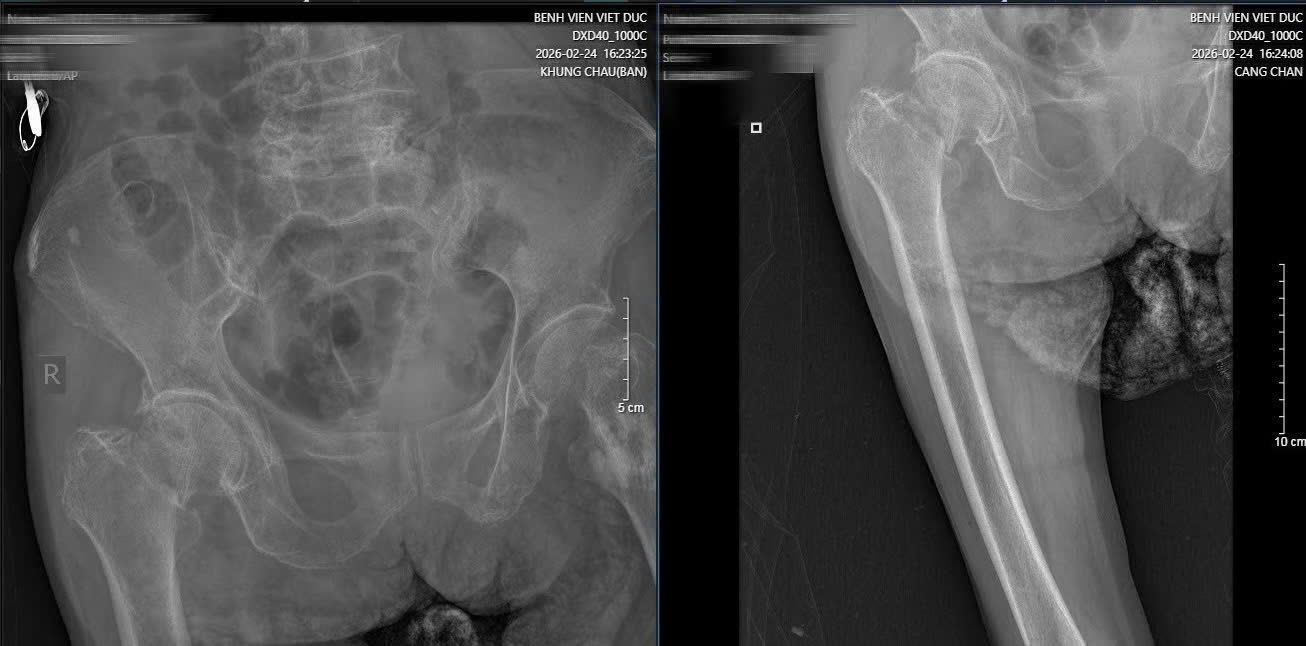

Ngoài ra, cụ còn mắc nhiều bệnh lý nền như vẹo cột sống, xẹp và trượt đốt sống thắt lưng, khiến việc điều trị trở nên khó khăn.

Hình ảnh phim X-quang cụ bà 89 tuổi nhập viện gãy cổ xương đùi phải và hình ảnh chụp CT ổ bụng và phát hiện khối u ruột non gây lồng ruột.